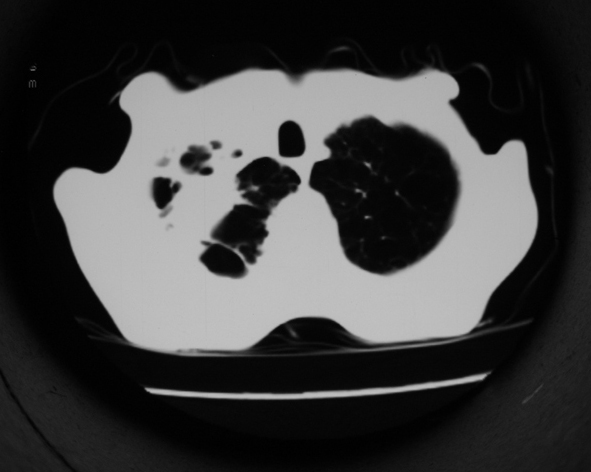

男53岁,咳嗽气短,以往身体健康.

右肺上叶多发多形态空洞及增殖灶,可见团块钙化,胸膜肥厚、粘连,考虑继发型肺结核可能性大

1.右肺上叶干酪性肺炎,2。肺气肿,肺大泡